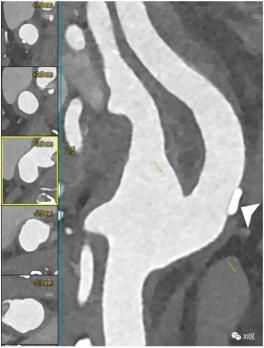

颈动脉分叉处的PCCT血管造影:轻度钙化动脉粥样硬化。PCCT血管造影显示超高清(源数据集;矩阵1024×1024;层厚/增量0.2/0.1mm;体素100 μm;卷积核Bv60;辐射剂量与使用第三代双源CT的同等颈动脉CT血管造影相当)颈动脉分叉处动脉壁增厚,近端颈内动脉处有轻度灶性钙化斑块(箭头所指)。

颈动脉分叉的PCCT血管造影:轻度非钙化动脉粥样硬化。PCCT血管造影显示了超高清(源数据集;矩阵1024×1024;层厚/增量0.2/0.1mm;体素100 μm;卷积核Bv60;辐射剂量与使用第三代双源CT进行的同等颈动脉血管造影相当)颈动脉分叉的纵向CPR成像,动脉壁有轻度弥漫性非钙化动脉粥样硬化。